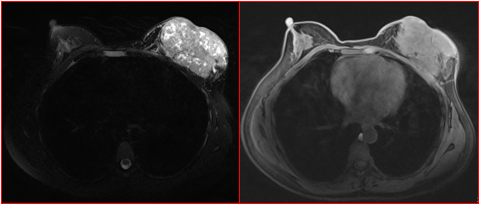

MG/CT:

乳腺炎:包括急、慢性乳腺炎和乳腺脓肿,多见于产后哺乳期妇女,急性乳腺炎常有典型的临床症状-红、肿、热、痛;若治疗不及时可形成慢性乳腺炎或乳腺脓肿。MG 表现片状致密影,边缘模糊,患处皮肤水肿增厚,皮下脂肪层模糊;MRI-T1WI 表现为片状低信号,T2WI 高信号,信号强度不均匀,边缘模糊,皮肤水肿、增厚,增强 MRI 通常表现为轻至中度强化,且以延迟强化为主。